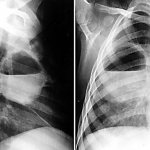

- рентгенография (на предмет патологии скелета);

- денситометрия (для определения плотности костной ткани);